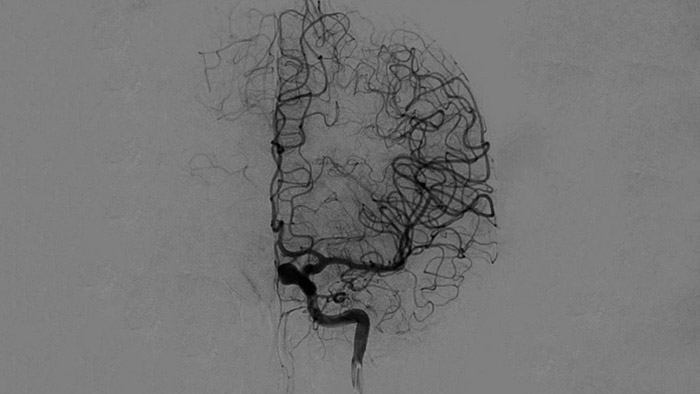

SmartCT Vaso IV

Comprobar la ubicación y la longitud del coágulo

SmartCT Vaso permite la visualización más allá del coágulo con imágenes periprocedimiento de las caras distales de los vasos en el accidente cerebrovascular isquémico. SmartCT Vaso es una técnica de adquisición basada en una TC de haz cónico y una inyección de contraste intrarterial. Permite la visualización más allá del coágulo con imágenes periprocedimiento de las caras distales de los vasos en el accidente cerebrovascular isquémico. Mediante el llenado retrógrado, se ven las estructuras de los vasos antes y después del coágulo. SmartCT Vaso 3D Roadmap puede utilizarse para visualizar los dispositivos de recuperación de coágulos.

Las referencias anatómicas apoyan una navegación 3D precisa

SmartCT image

SmartCT Roadmap proporciona referencias anatómicas para apoyar la navegación precisa de la aguja guía, el catéter y el dispositivo al coágulo.